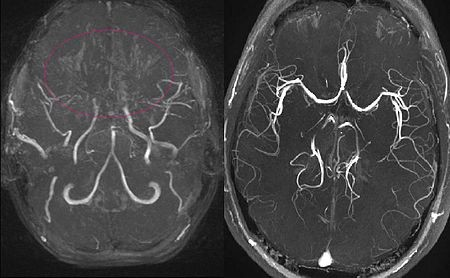

모야모야병은 어떻게 진단되나요?

모야모야병은 CT, MRI, MRA, 뇌혈관 조영술 등의 영상 검사를 통해 진단됩니다. 특히, 뇌 자기공명영상(MRI 및 MRA)은 초기 진단에 중요한 역할을 하며, 뇌혈류량 측정을 위해 관류 MRI나 다이아목스를 이용한 뇌스캔이 추가로 사용될 수 있습니다.